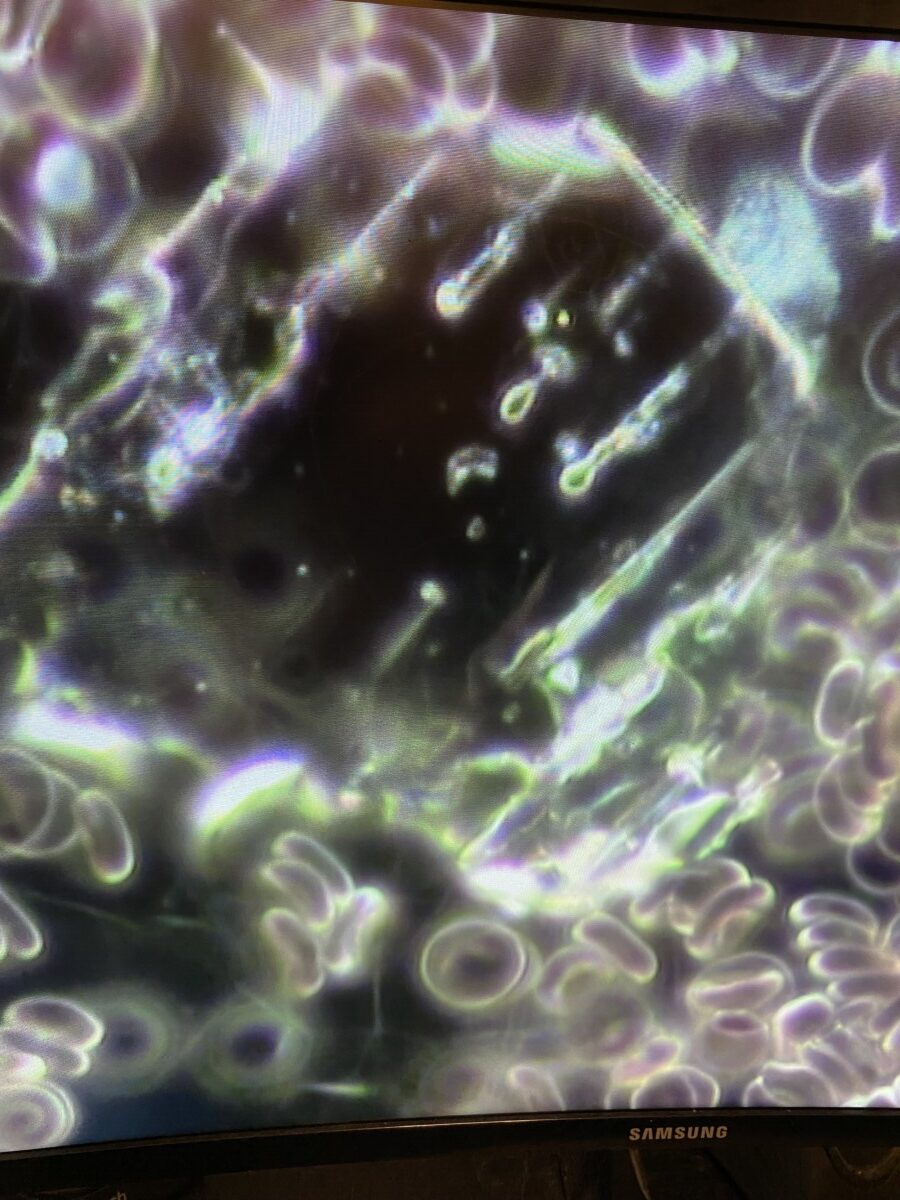

These are pictures from the blood of our client.

Large amyloid deposit / circulating plasma clots

The clots we are seeing in Long COVID are not normal clots. They contain large anomalous amyloid deposits. They are not normal clots. They are aggregated blood cells which have been transformed into aggregated fibrils! “Given that blood clots can block microcapillaries and thereby inhibit oxygen exchange, we here investigate if the lingering symptoms that individuals with Long COVID/PASC manifest might be due to the presence of persistent circulating plasma micro clots that are resistant to fibrinolysis.”